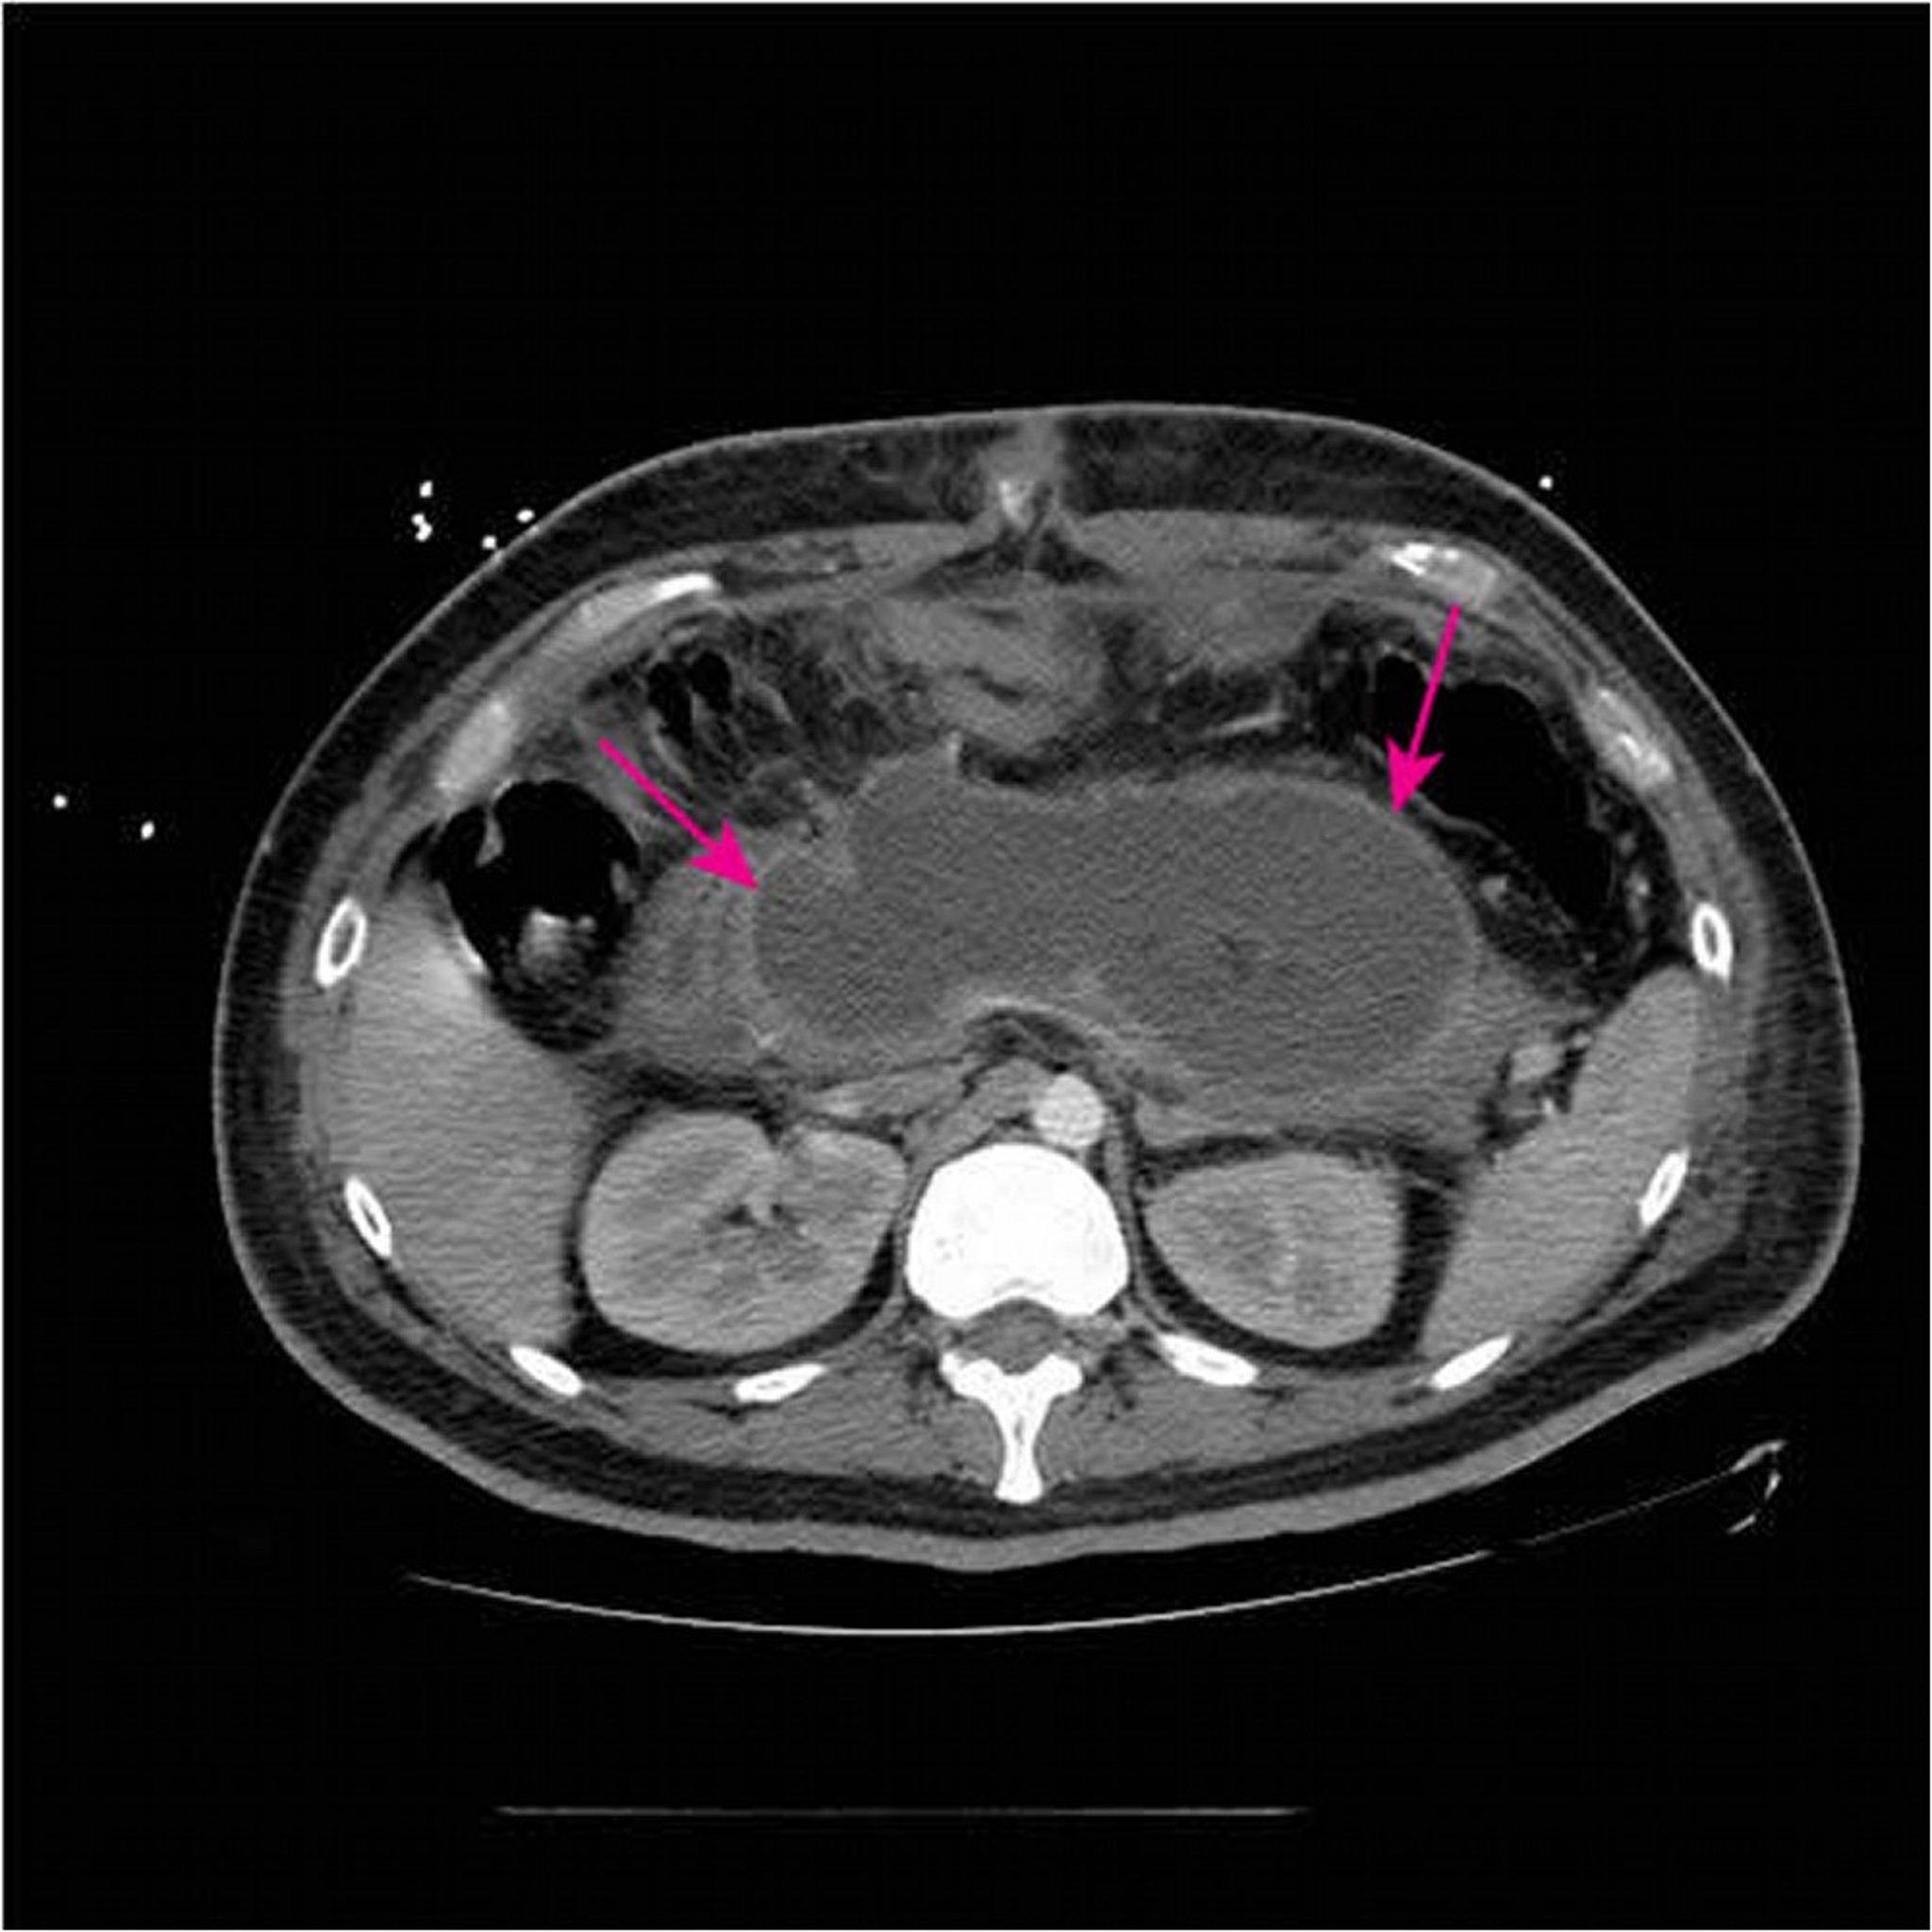

Acute Necrotizing Collection

This CT scan with IV and oral contrast shows a large acute necrotizing collection (arrows) replacing most of the pancreatic tissue < 4 weeks from initial presentation of necrotizing pancreatitis.

Image courtesy of Sonam Rosberger, MD.